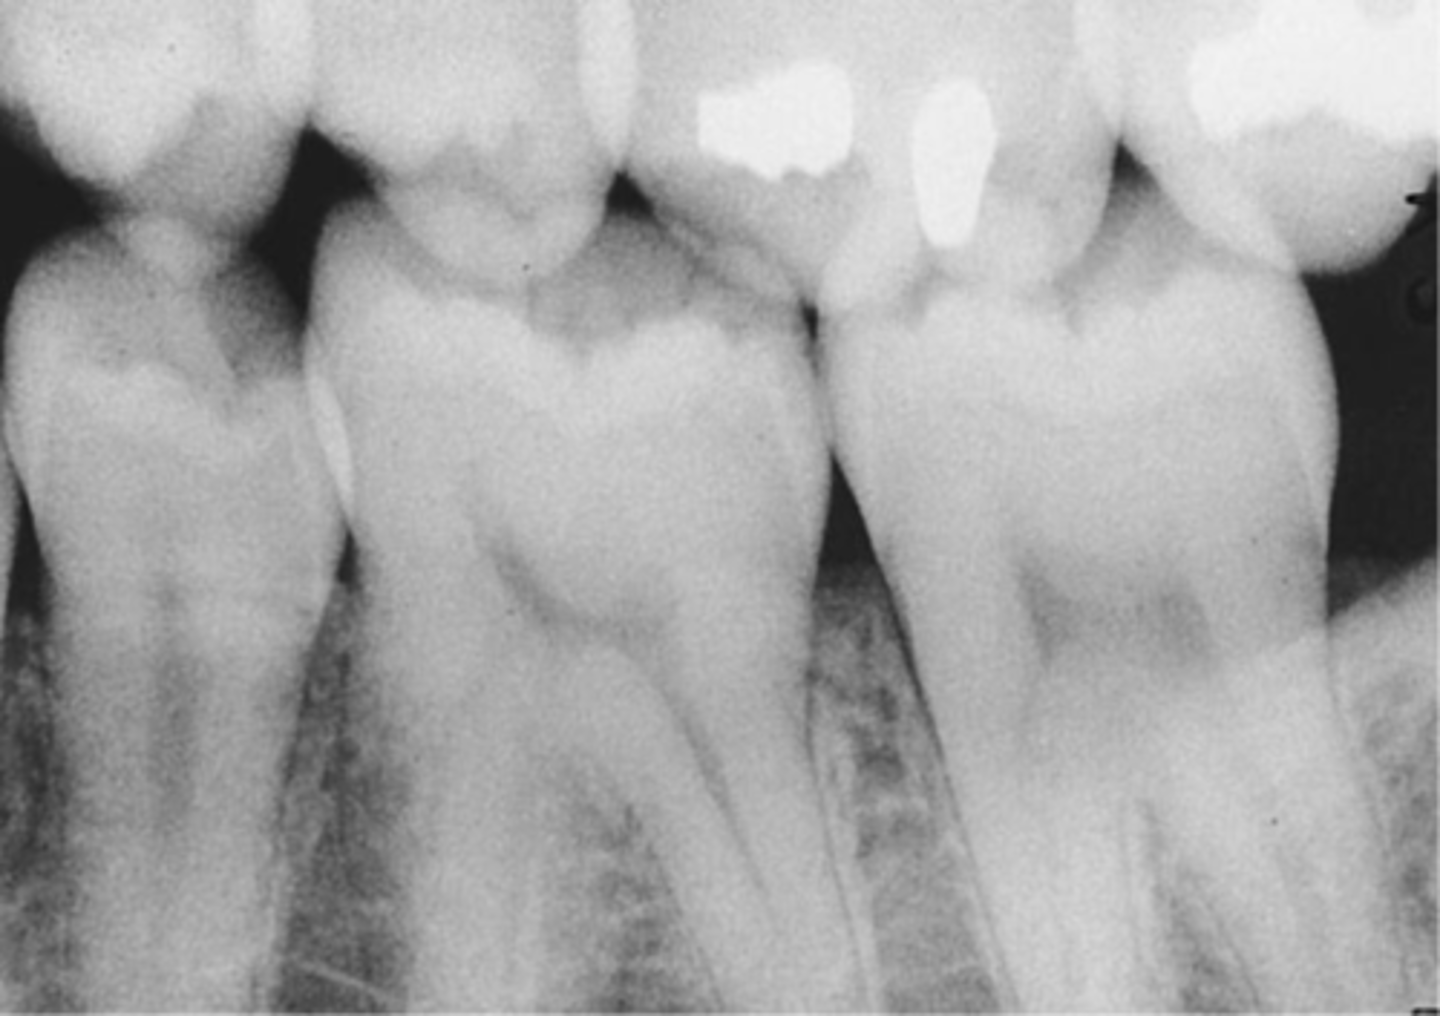

What causes one arch to be more visible than the other in a bitewing image?

Incorrect vertical angulation.